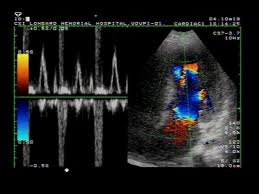

نوعی دیگر اکو به نام اکوی داپلر میباشد که برای تشخیص جهت و اندازهگیری سرعت جریان خون در داخل قلب و عروق بزرگ استفاده میشود ، در اکو داپلر رنگی ، تصاویر رنگی (قرمز و آبی) ایجاد میشودکه روش دقیقی در ارزیابی ناهنجاریهای مادرزادی قلبی و اختلالات دریچهای( تنگی ویا گشادی) می باشد.